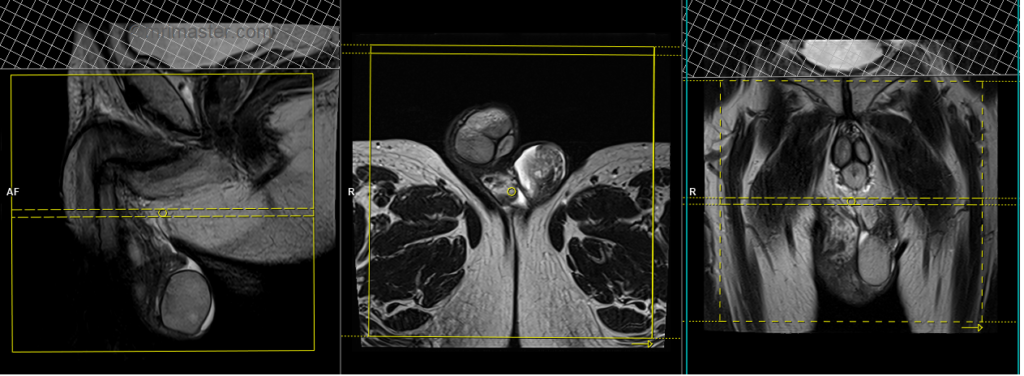

T1 tse axial 3mm SFOV

Plan the axial slices on the sagittal plane; angle the positioning block horizontally across the scrotum (parallel to the penile shaft). Check the positioning block in the other two planes. Ensure an appropriate angle is given in the coronal plane (horizontally across the testis). The slices must be sufficient to cover the scrotum from the prostate down to 1 cm below the scrotum.

T2 tse axial 3mm SFOV

T2 tse coronal 3mm SFOV

Plan the coronal slices on the axial plane and angle the positioning block perpendicular to the penile shaft. Check the positioning block in the other two planes. An appropriate angle must be given in the sagittal plane (vertically across the scrotum). Slices must be sufficient to cover the entire scrotum from the penis to the anal canal.